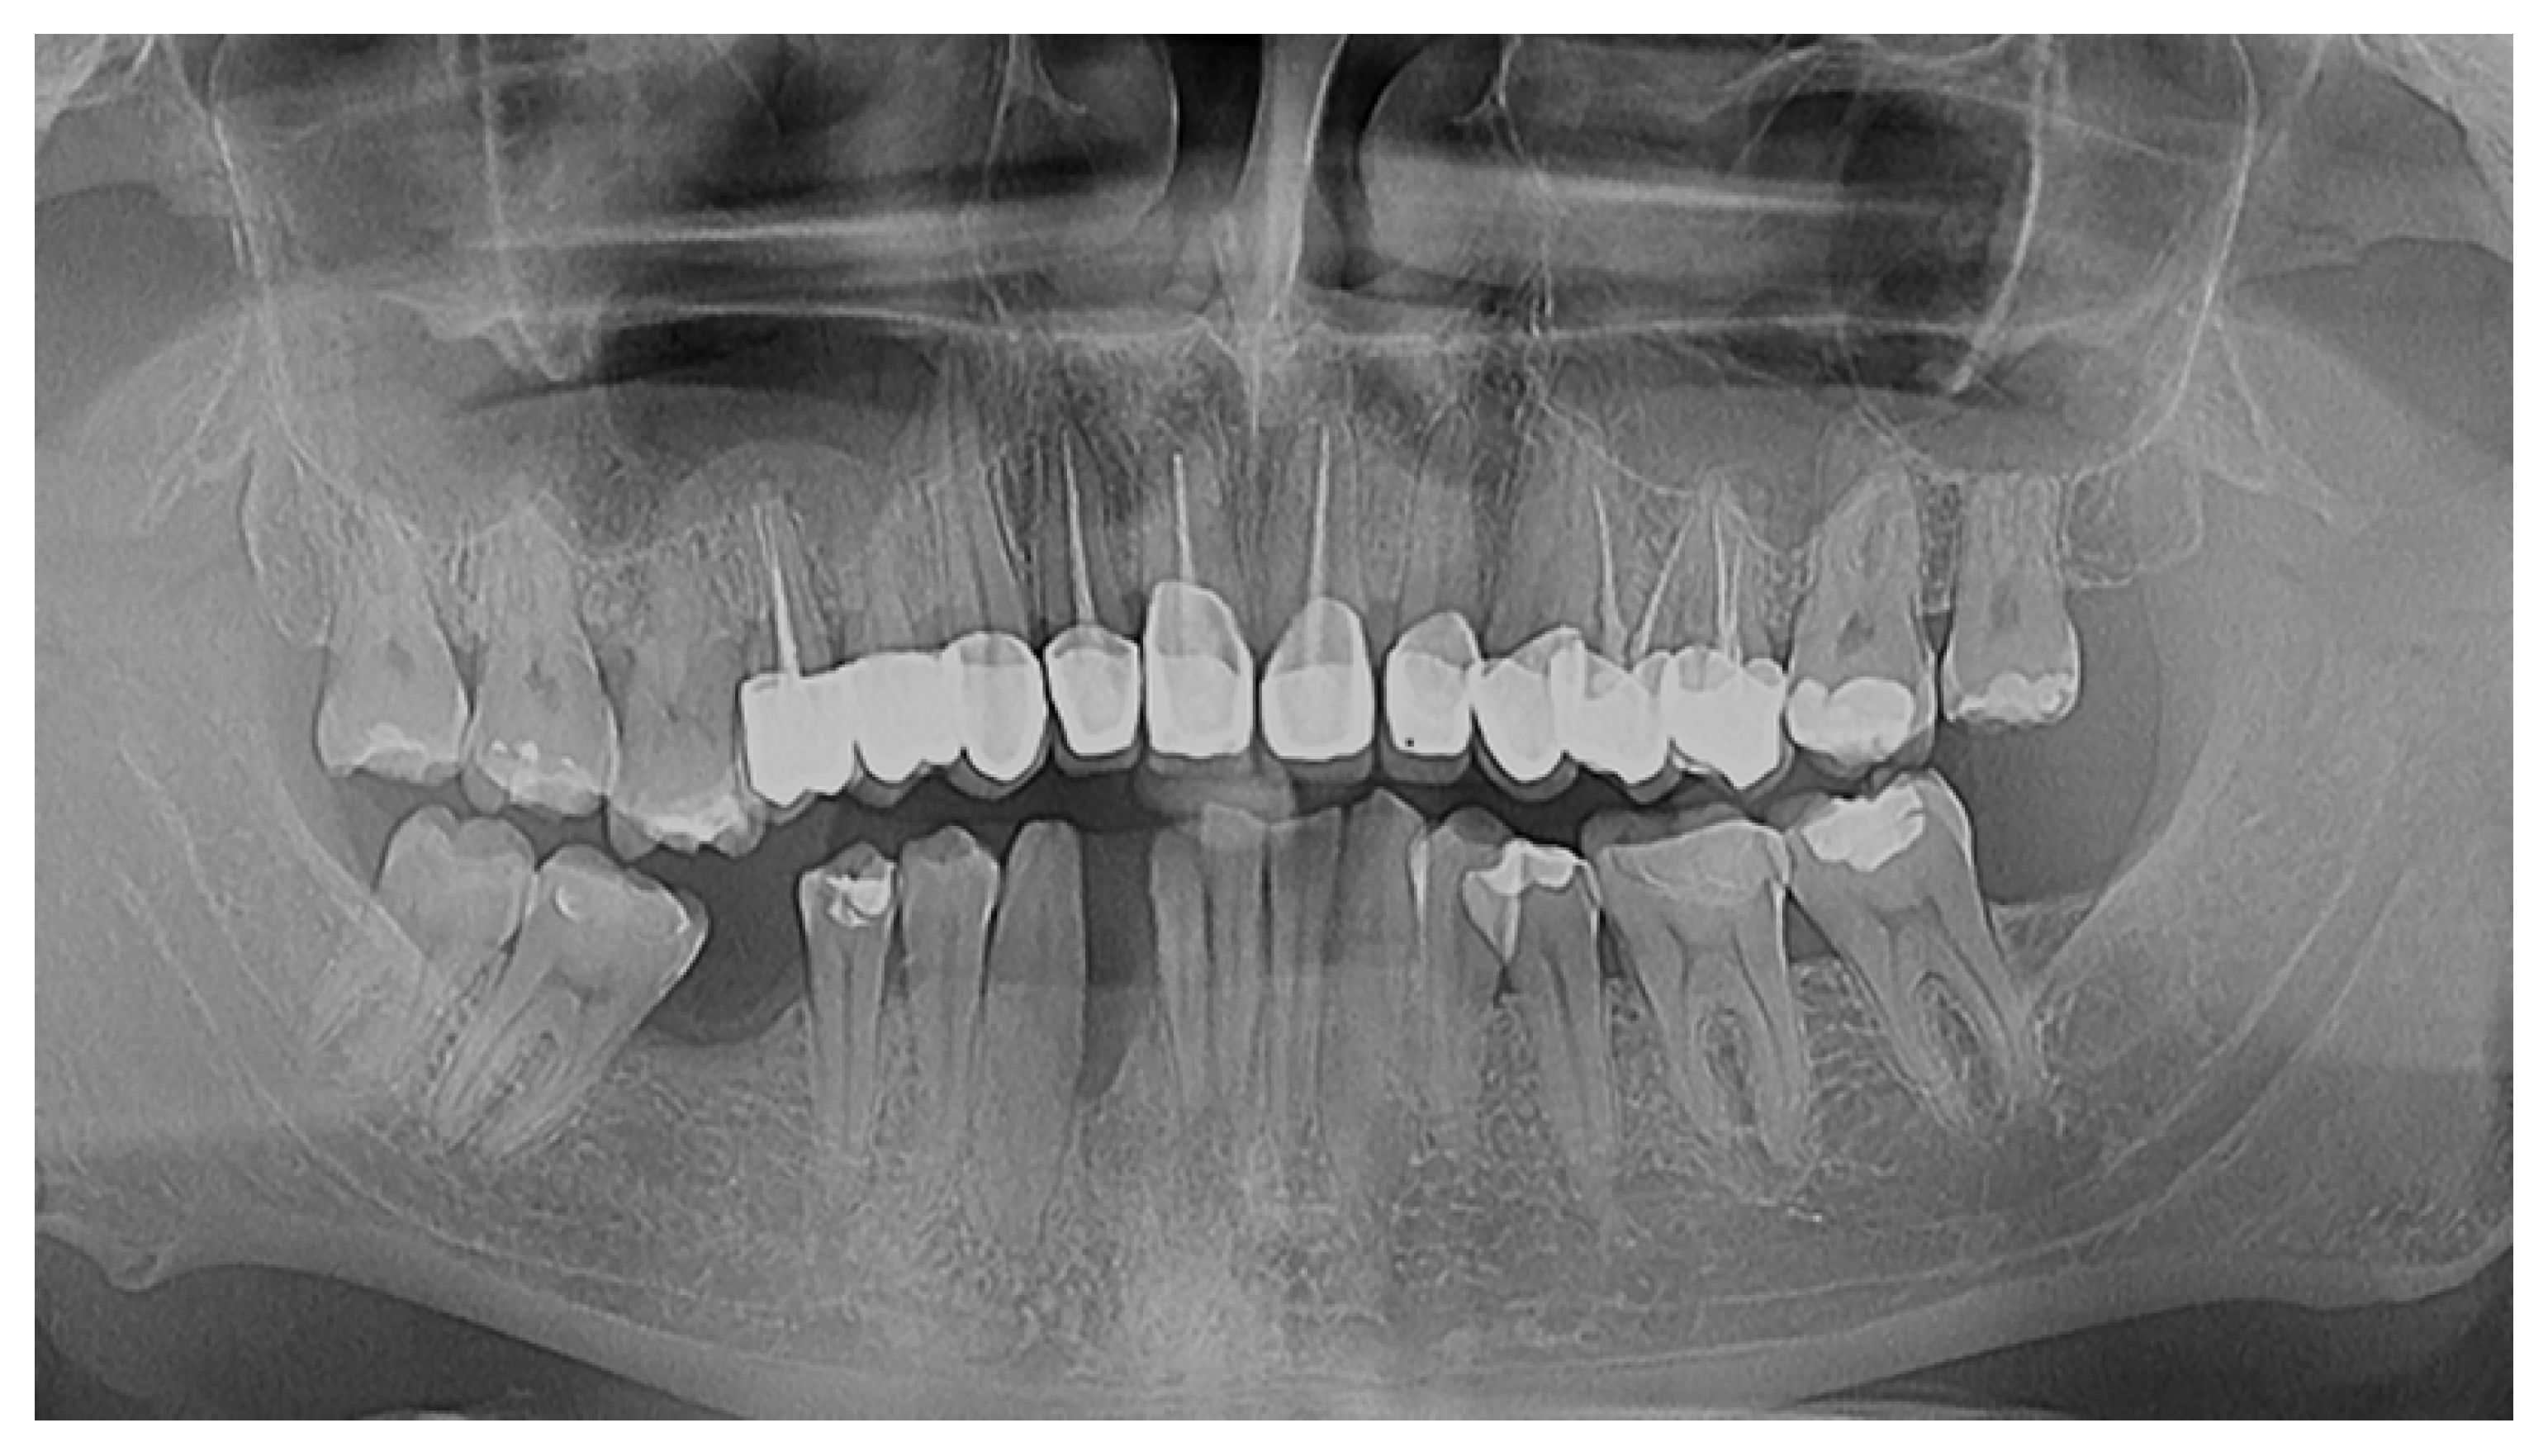

2.1. Patient Presentation

2.2. Initial Consultation